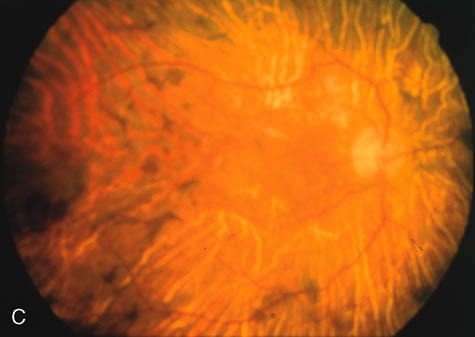

Of more clinical importance is the role of FA in the diagnosis and treatment of cystoid macular edema (CME) (Fig. 1C and D). Stereoscopic FA indicates that the leakage, which may be diffuse or have the typical petaloid stellate appearance of CME, can come from the perifoveal retinal capillaries, from the choroid through the RPE, or from a combination of both sources.4 With the recent suggestion that CME in RP may be successfully treated with acetazolamide,5, 6 FA is thus important to document the diagnosis of CME, establish the origin(s) of leakage, and follow patients during and after therapy.